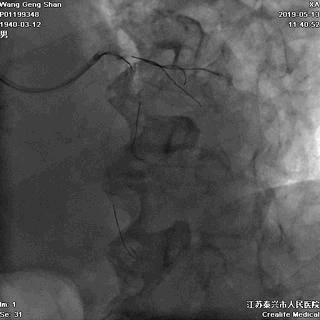

05 LM-LAD支架植入

右头位定位

蜘蛛位定位

LCX球囊拘禁,主支支架释放

回撤LCX球囊

支架球囊再次扩张支架